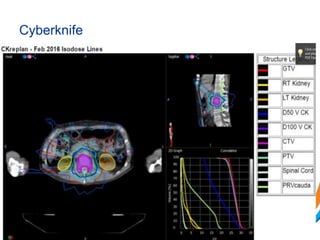

VMAT

Cyberknife